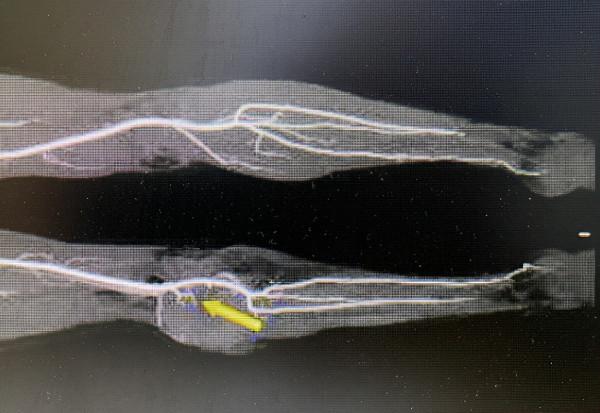

來到我院後,王女士找到鄭大偉主任。鄭主任為患者安排檢查,CTA檢查顯示膕窩後側約15*12*13cm巨大腫瘤,並已壓迫膕血管,常規手術切除腫瘤難度很大,稍有不慎損傷血管,將導致肢體缺血、截肢的後果。

鄭大偉主任、黎章燦醫生及其團隊經術前討論,決定採用顯微外科技術進行腫瘤切除修復,既可以徹底切除病變,也可以保留肢體血運,並制定了周密的手術方案。手術團隊在顯微鏡下,利用嫻熟的顯微外科技術在膕動脈外膜下剝離,剝繭抽絲般完整切除腫瘤,並且保持血管完好無損,腫瘤切除後形成的巨大創面,採用股前外遊離皮瓣進行了修復,手術歷經6.5小時順利完成,目前患者已恢復出院。